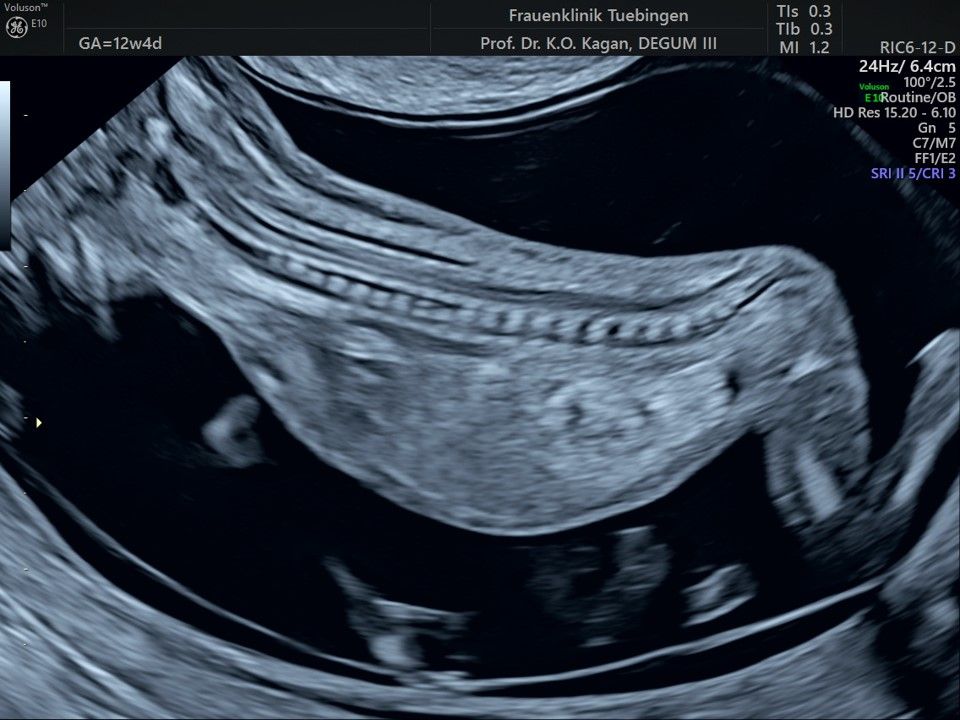

Das Ergebnis der Ultraschalluntersuchung ist wegweisend. Dabei wird der Fet vermessen, die Organe werden untersucht und die sonographischen Marker zur Risikoberechnung für Chromosomenstörungen werden beurteilt. Das sind: die Nackentransparenzdicke, Nasenbein sowie der Blutfluss in der rechten Herzhälfte und im Ductus venosus, einem Gefäß in der Leber des Feten.

Im Rahmen des Ersttrimester-Screenings untersuchen wir die Organe des Feten mittels Ultraschall. Dabei machen wir auch gerne ein Bild für Sie.

Obwohl der Fet zu diesem Zeitpunkt erst zwischen 5 und 8cm groß ist, lassen sich bereits etwa die Hälfte aller schwerwiegenden Fehlbildungen erkennen bzw. ausschließen. Sollten wir eine Auffälligkeit sehen, werden wir mit Ihnen den Befund und das weitere Vorgehen ausführlich besprechen.